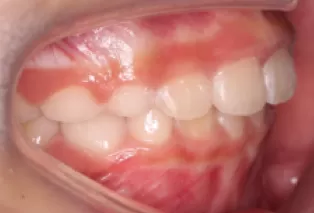

Photos intra-orales